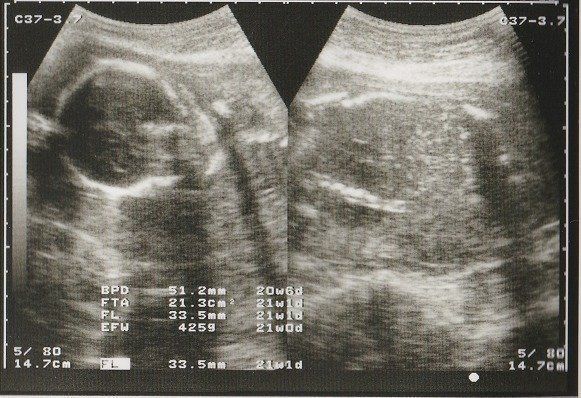

妊娠21週目のエコー写真 赤ちゃんが激しく動くようになる

FL(大腿骨長)が30mmを超えました。人体で一番長い骨である大腿骨の長さを測って、赤ちゃんの成長をチェックしています。

妊娠6カ月になると、おなかも多くなり、赤ちゃんの動きも激しくなってきました。